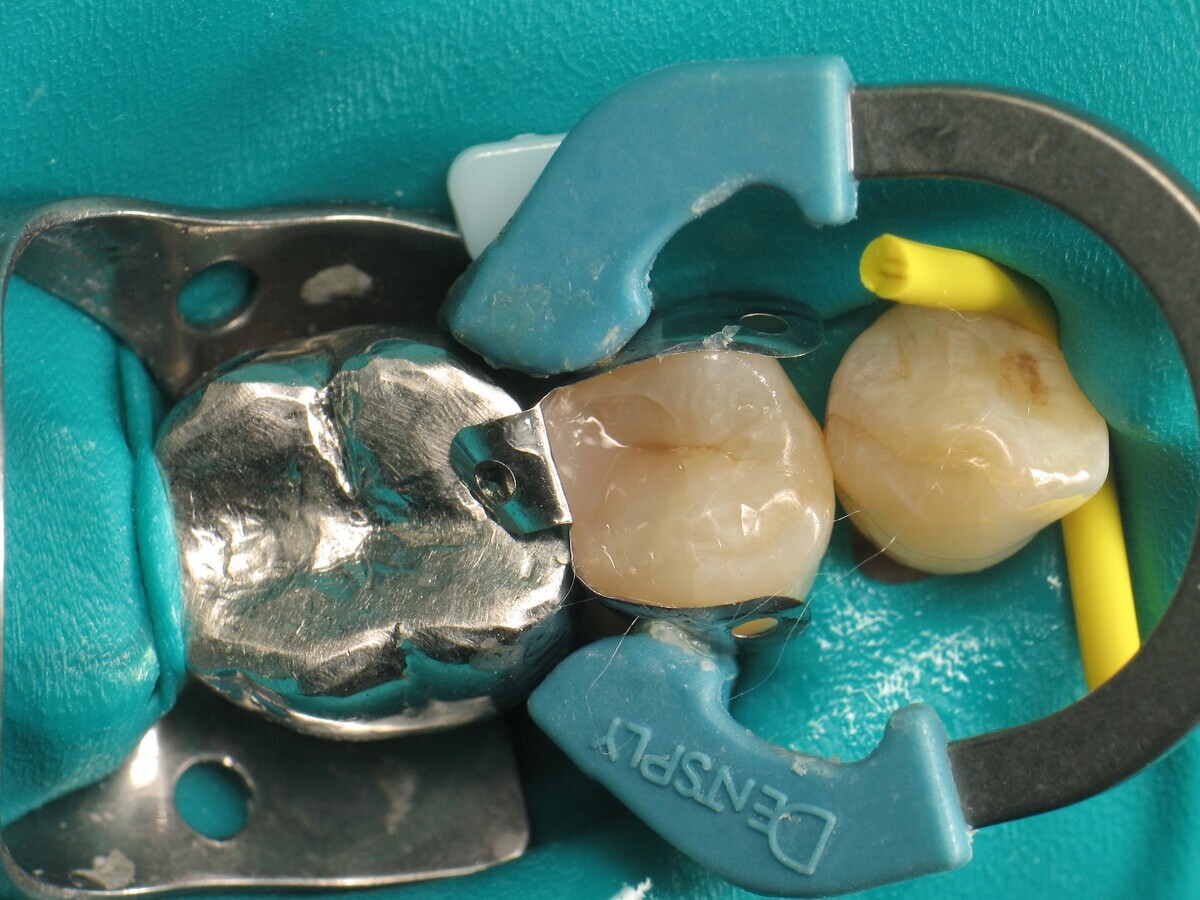

El diente se aísla con un dique de goma (Figura 2).

Figura 02. Instalación del dique.

Para obtener una pared distal anatómicamente correcta, se colocan una matriz, una cuña y un anillo (Figura 4).

Figura 04. Instalación de matriz proximal.